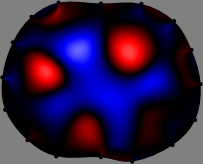

Figs. 3 and 4 compare the performance of the proposed FER method in (20) with the standard regularized least-squares method ((19) when is the identity matrix). The regularization parameter of the standard method was heuristically chosen for its best performance, and the parameter of the FER method was set to be one of three different values . The injection current was 1 mA at 100 kHz, and the frame rate was 9 frames per second. The reference frame at was obtained from the maximum expiration state. The measured data, , represent the voltage differences between each time and . The blue regions, which denote where conductivity decreased by inhaled air, increased during inspiration and decreased during expiration. The FER method with was clearly more robust than the standard method that produced more artifacts originated from the inversion process.

| Standard | |

||||||||||

| FER () | |